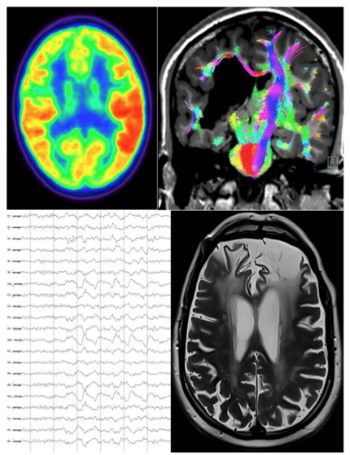

Tal y como explica la doctora Carla Anciones, de la Unidad de Epilepsia del Hospital La Luz, "la epilepsia es una enfermedad multifactorial, que puede responder a múltiples causas. Cada día, los avances científicos nos revelan una mayor implicación del papel de la genética y de las enfermedades autoinmunes. Sin embargo, son muy frecuentes las lesiones estructurales focales (malformaciones del desarrollo de la corteza cerebral, lesiones vasculares, tumores, traumatismos, entre otras) y los trastornos metabólicos. Para detectarlas, se utilizan diversas técnicas diagnósticas que deben ser ejecutadas y evaluadas por personal especializado. Entre estas se incluyen técnicas de neurofisiología (electroencefalografía), neurogenética, neurorradiología, medicina nuclear y neurocirugía, entre otras".